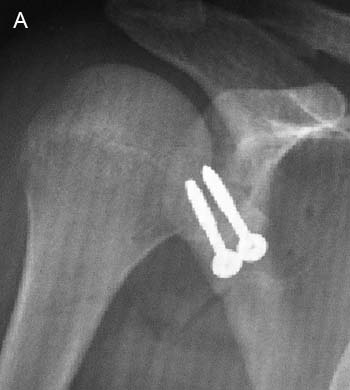

Figura 3: Radiografía de Hombro posterior a Cirugía de Latarjet. A: Radiografía anteroposterior, B: radiografía axial de escápula. Se observan 2 tornillos maleolares.

Lafosse et al.33 plantean realizar este procedimiento en forma completa vía artroscópica, no presentando mayores complicaciones, obteniéndose resultados buenos y excelentes con un seguimiento a corto y mediano plazo (Fig. 3 y 4).